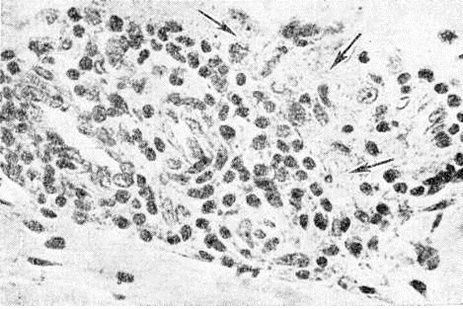

Гистологический исследование биопсийного материала имеет важное значение для установления диагноза и прогноза болезни. Биопсии подвергаются участки поражённой кожи, изредка — поверхностно расположенные нервы. Морфологически изменения при Лепра проявляются в виде гранулем двух полярных типов — лепроматозного (LL) и туберкулоидного (ТТ), а также трёх групп — погранично-туберкулоидной (ВТ), пограничной (ВВ) и погранично-лепроматозной (BL).

Гистологически лепроматозный тип характеризуется лепроматозной гранулемой кожи, которая представляет инфильтрат, расположенный в сетчатом слое, отделённый от эпидермиса непоражённой зоной коллагеновой ткани. Основными клеточными элементами лепроматозной гранулемы являются лепрозные клетки; кроме того, наблюдаются отдельные плазматические, лимфоидные клетки, единичные фибробласты, многоядерные пенистые клетки (цветной рисунок 1—6). Лепрозные клетки относятся к макрофагам, характеризуются бледным ядром и «пенистой» цитоплазмой (рисунок 5) за счёт содержания липидов. Лепрозный макрофаг на ранних стадиях содержит жирные кислоты, фосфолипиды, ненасыщенные липиды; на стадии развития процесса преобладают нейтральные жиры и кислотные липиды. Большинство исследователей считает, что основная масса липидов представляет собой продукт метаболизма и распада микобактерий Лепра. Наиболее характерная особенность лепрозного макрофага — нахождение и размножение в нем большого количества микобактерий Лепра, то есть явление незавершённого фагоцитоза (смотри полный свод знаний). В цитоплазме лепрозной клетки выявляется высокий уровень окислительно-восстановительных ферментов, кислой фосфатазы, неспецифической эстеразы и не обнаруживается активность липазы. Для гистологический картины LL характерно также наличие капилляров со значительным сужением их просвета за счёт пролиферации и набухания эндотелиальных клеток, содержащих большое количество микобактерий типа «глоби». Кожные нервы пронизаны инфильтратами из микробосодержащих клеток (цветной рисунок 7 и 10). Микобактерии обнаруживаются также в клетках эндоневрия. В лепроматозных поражениях большой давности отмечается частичное или полное разрушение придатков кожи (фолликулов волос, сальных и потовых желёз).

При туберкулоидном типе патологический процесса сформировавшийся инфильтрат может быть массивным, занимающим все слои собственно кожи, или располагаться отдельными очагами. Характерно разрушение субэпидермального слоя коллагеновой ткани с расположением гранулемы непосредственно под эпидермисом с эрозированием последнего. Основную массу гранулемы составляют эпителиоидные клетки (смотри полный свод знаний), расположенные в центре и окружённые по периферии валом из лимфоидных клеток (смотри полный свод знаний Лимфоциты), встречаются гигантские многоядерные клетки типа Лангханса (смотри полный свод знаний Гигантские клетки), в небольшом количестве обнаруживаются плазматические клетки (смотри полный свод знаний), тучные клетки (смотри полный свод знаний), фибробласты. В период обострения в гранулеме наблюдается обилие полиморфно-ядерных лейкоцитов (смотри полный свод знаний). Клеточные элементы не содержат микобактерий и липидов. Характерно утолщение нервных стволов за счёт массивной инфильтрации эпителиоидными клетками.

Морфологически структуры, содержащие элементы, характерные для обоих типов Лепра и являющиеся как бы переходной стадией между полярными типами, характерны для пограничной Лепра При недифференцированной Лепра наблюдается картина банального хронический воспаления (смотри полный свод знаний) без специфических изменений. Основными гистологический критериями, определяющими принадлежность к классификационным группам Ридли — Джоплинга, являются следующие морфологический особенности инфильтрата. 1. Клеточный состав гранулемы. В верхней половине спектра (ТТ, ВТ и ВВ) характерно наличие эпителиоидных клеток (цветной рисунок 8) и для ТТ — многоядерных (гигантских) клеток типа Лангханса (цветной рисунок 9). При ВВ эпителиоидные клетки часто отделены друг от друга отёком. В нижней части спектра (BL и LL) эпителиоидные клетки уступают место макрофагам, цитоплазма которых по мере приближения к типу LL становится более плотной, пенистой и содержит жир. 2. Плотность популяций микобактерий. Количество микобактерий возрастает пропорционально от верхней части спектра к нижней. В числовом выражении показатель бактериальной насыщенности лепроматозного инфильтрата для ТТ, ВТ, ВВ, BL и LL составляет 0/1; 0/2,5; 3/4,5; 4/5,5; 5/6,5 соответственно. 3. Количество и топография лимфоцитов в гранулеме. Для ТТ и ВТ свойственно высокое содержание лимфоцитов, расположенных в виде плотного бордюра вокруг массы эпителиоидных клеток. При ВВ и LL количество лимфоцитов чаще снижено, они рассеяны по гранулеме и не образуют вала. 4. Поражение кожных нервов. Для туберкулоидной части спектра характерно значительное утолщение нерва за счёт массивного инфильтрата (повышение максимального диаметра пучка при ТТ). Для ВВ и BL патогномоничны изменения периневрия в виде луковичной кожуры (onion skin) за счёт расслоения его инфильтратом из лимфоцитов, плазмоцитов (при В В) или бактериосодержащих макрофагов (при BL). 5. Отношение к эпидермису. При ТТ и ВТ гранулема располагается непосредственно под эпидермисом и может эрозировать его. При ВВ, BL и LL между инфильтратом и эпидермисом постоянно остаётся непоражённая зона толщиной 30 — 75 микрометров — так называемый слой Ипа, состоящий из коллагеновой ткани.